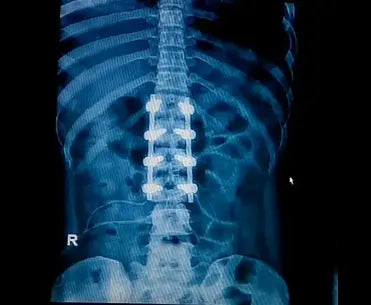

Spinal Stenosis.

What is Lumbar Spinal Stenosis and understand non surgical alternatives

Lumbar spinal stenosis is a disorder that may cause low back and/or leg pain. Lumbar spinal stenosis is a narrowing of the spinal canal in your lower back that may cause pain or numbness in your legs. Its treatment can include physical therapy, medicine, and sometimes surgery. Other modalities, such as Transcutaneous Electrical Nerve Stimulation, Pulsed Electro Magnetic Field Therapy, ultrasound, heat or cold therapy, and traction, can also be effective. PEMF therapy can be effectively used as a drug-free to alleviate spinal stenosis pain. By its very nature, it is based on the principles of low-field magnetic stimulation to promote self-healing in the body. PEMF devices emit pulses at low frequencies, which encourages the stimulation of cells, regenerates affected tissues, and brings relieving effects so that one no longer feels nagging sensations associated with lumbar or cervical stenosis.